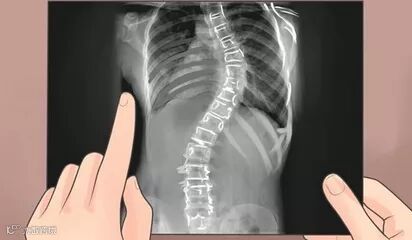

正常人的脊柱从背后看应该呈一条直线且躯干两侧对称,如果正面存在双肩不等高或后背左右不平,就应怀疑“脊柱侧弯”。青春期作为人体的第二个生长高峰,脊柱生长较快,原本轻微的脊柱侧弯此时可能加速病变,其中“青少年特发性脊柱侧弯”的发病率较高,约占2%~3%,因此务必早发现、早治疗。

❖侧弯角度<10°的患儿可以暂时不予治疗,日常生活中注意纠正不良姿势,每4~6个月进行体格检查,必要时拍摄全脊柱X光片。

目前,手术治疗的方式是通过钛合金螺钉和棒等内固定技术将弯曲的脊柱慢慢拉直固定,然后将移植骨覆盖于脊柱后方使弯曲的脊柱长在一起,从而达到预防脊柱弯曲加重、改善心肺及消化功能的目的。脊柱侧弯矫正手术的技术成熟,术后瘫痪的概率极低,伤口感染等并发症发生率也仅为0.5%~1%;患儿在术后5~7天可下地活动,1~2周内出院,多数患儿在术后6~8周可游泳锻炼并上学,3个月后可慢跑,1年左右可参加非接触对抗的体育活动。